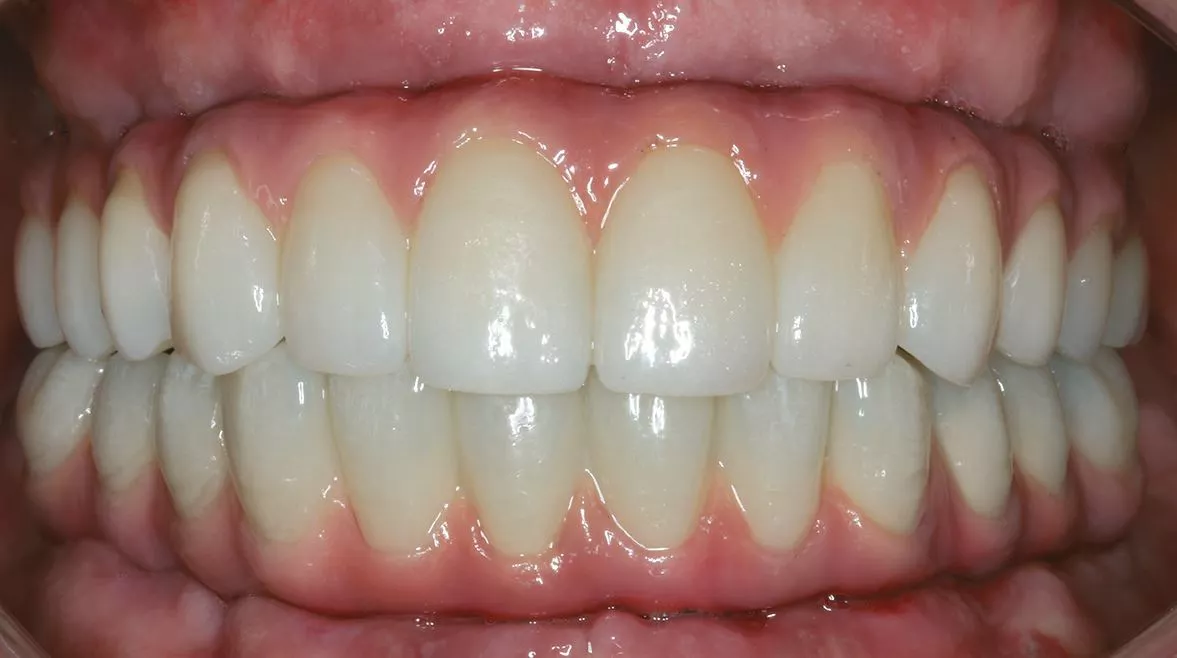

In einem nächsten Schritt kann man dann eine geführte Einzelzahnsofortversorgung durchführen. Der gezeigte Fall stellt den Abschluss einer solchen Entwicklung dar. Die Plattform erleichtert dem Anwender auch komplexe Versorgungen mit vertretbarem Aufwand sicher und mit einem geringen Komplikationsrisiko zu erreichen (Abb. 13-14). Nach einer Einarbeitung mit dem digitalen Workflow, können dann wieder je nach Investitionsvolumen Arbeitsschritte in der eigenen Praxisstruktur etabliert werden, um den Leistungsumfang wieder stärker in der praxiseigenen Prozesskette einzubinden.

im Oberkiefer bei dünner Kortikalis oftmals durch ein festeres Einpressen positioniert werden. Im Unterkiefer wird über die Hülse für den Fixationspin in der Regel eine Vorbohrung notwendig. Nach der genauen Lagesicherung der Navigationsschablone kann dann die komplette Bohrerabfolge geführt bis zur Implantatinsertion angewendet werden. Im Anschluss werden die bei der Planung definierten geraden und angulierten Abutments eingesetzt und die Titanzylinder für das Einkleben des Provisoriums fixiert [1]. Nach dem Einkleben der Zylinder in das Provisorium muss diese nochmals ausgearbeitet werden und die Sofortversorgung ist abgeschlossen (Abb. 11-12).